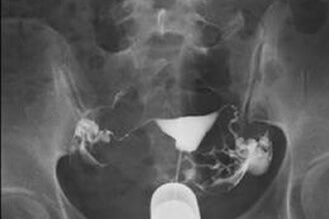

正常な子宮卵管の造影,子宮卵管は2本とも正常

膣鏡で膣を開き、造影剤注射器を子宮頸部に固定して造影剤を子宮腔内に入れます。2本の子宮卵管が正常ならば造影剤は子宮腔から2本の子宮卵管を通り骨盤腔に流れ込みます。X線撮影により造影剤が骨盤腔に流れたかがわかります。検査過程は約10分です。